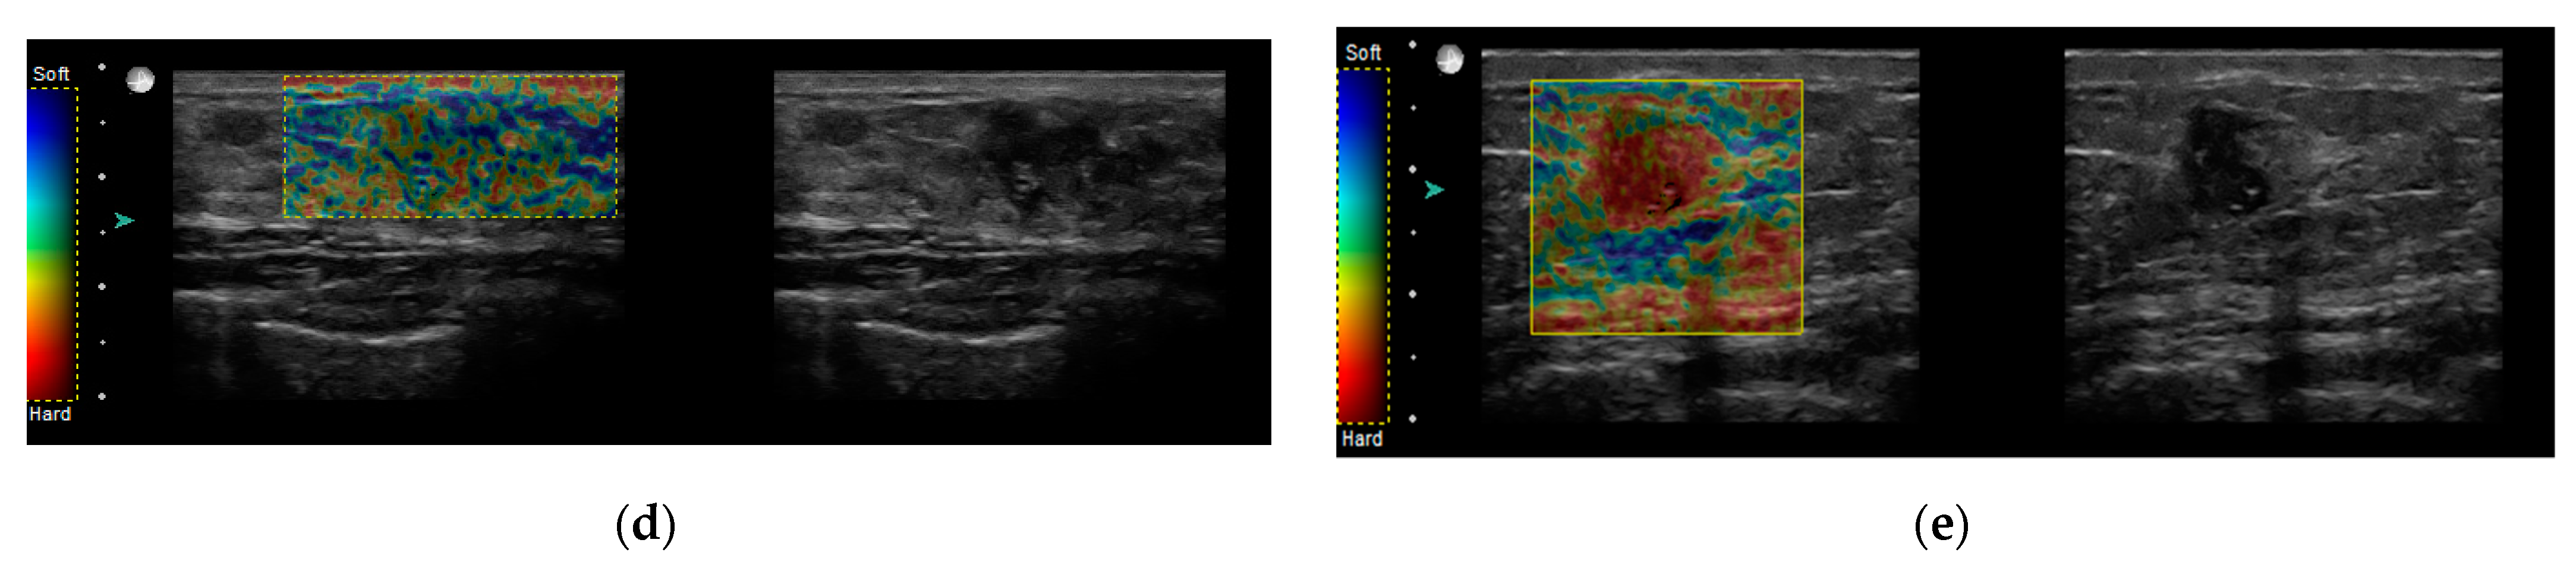

2.2. Sonoelastography

- Soft (incorporate: Tsukuba1,Tsukuba2, E max < 80 kPa)

- Intermediate (incorporate: Tsukuba3, E max > 80 kPa < 160 kPa)

- Hard (incorporate: Tsukuba 4,Tsukuba5, E max > 160 kPa)